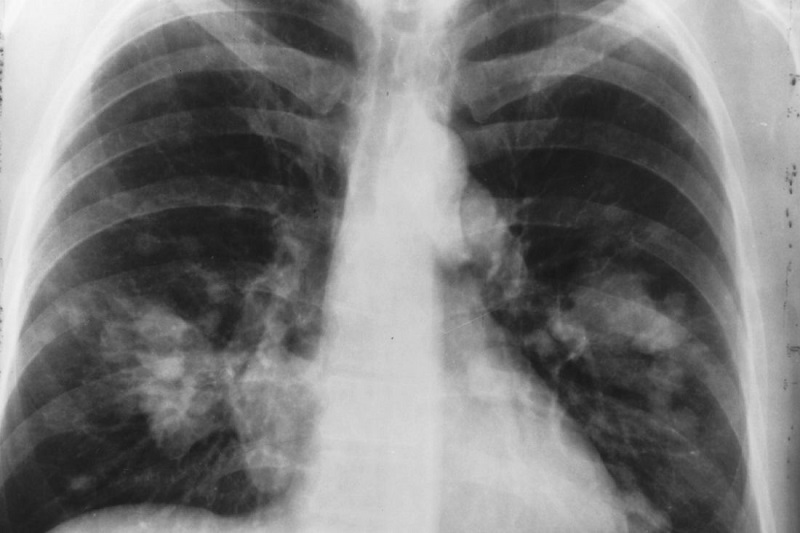

سرطان ریه نوعی بیماری بدخیم است که در سلولهای ریه ایجاد میشود. تشخیص آن معمولاً با سیتیاسکن، PET Scan، نمونهبرداری (بیوپسی) و آزمایشهای تکمیلی انجام میشود. تشخیص زودهنگام نقش مهمی در افزایش شانس درمان دارد.

پرتودرمانی با استفاده از اشعههای پرانرژی انجام میشود که سلولهای سرطانی را هدف قرار میدهد. این درمان معمولاً بهصورت سرپایی و بدون درد انجام میشود.